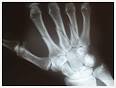

Metabolismo Oseo. El hueso es un órgano firme, duro y resistente que forma nuestro esqueleto. Está formado prinicplamente por tejido óseo, un tipo especializado de tejido conectivo constituido por células, y por componentes extracelulares calcificados organismo.